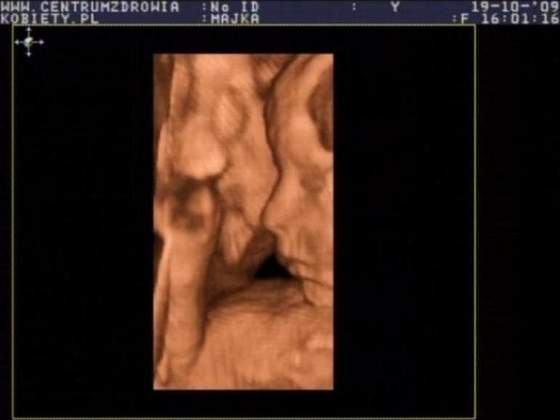

Co do USG jestem zbyt padnięta by to opisać ale będzie Córeczka jest zdrowitka i waży 689 gram :-) Normalnie jestem szczęśliwa :-):-):-):-):-):-):-):-)

no wykapana mamusiaJakims cudem udało mi się zrobić 2 screeny z usg ;-)

A więc to moja mała księżniczka

Zobacz załącznik 173968Zobacz załącznik 173969